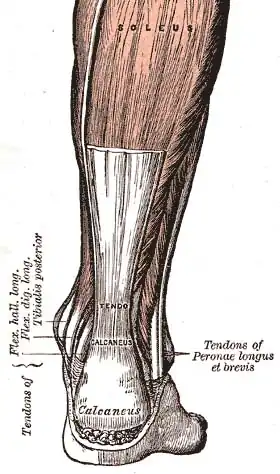

In a 2012 study, researchers examined the risk long-time high heel wearers would have in regards to calf Muscle fascicle length and strain.[32] The control group consisted of women who wore heels for less than ten hours weekly and the experimental group consisted of women who wore heels for a minimum of forty hours weekly for at least two years. The experimental group was told to walk down a walkway barefoot and in heels. In contrast, the control group walked barefoot as cameras recorded their movements to calculate muscle fascicle lengths. The data showed that wearing heels shortened the size of the medial gastrocnemius (MG) muscle bundles in the calf significantly as well as increasing stiffness in the Achilles tendon. The experimental group also demonstrated a more significant strain on the muscle fascicles while walking in heels because of the flexed position the foot is forced into. The researchers estimated that when wearing heels, the estimated fascicle strains were approximately three times higher, and the fascicle strain rate was about six times higher. Additionally, they concluded that the long-term usage of high heels could increase the risk of injuries such as strain, discomfort, and muscle fatigue.

Diagram of an Achilles tendon

Diagram of an Achilles tendon -